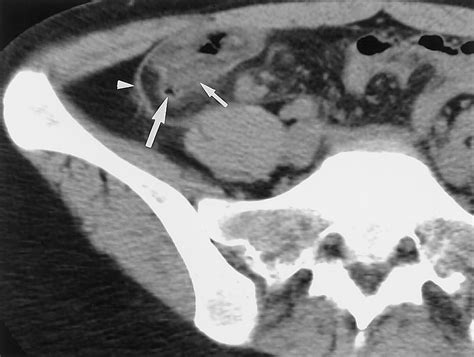

Case Study 3: Trauma

A 30-year-old patient involved in a motor vehicle accident presents with abdominal pain and tenderness. A CT scan reveals retroperitoneal fat stranding, a hepatic laceration, and a splenic hematoma. These findings are consistent with blunt abdominal trauma, and the patient is managed surgically.

Trauma CT Scan